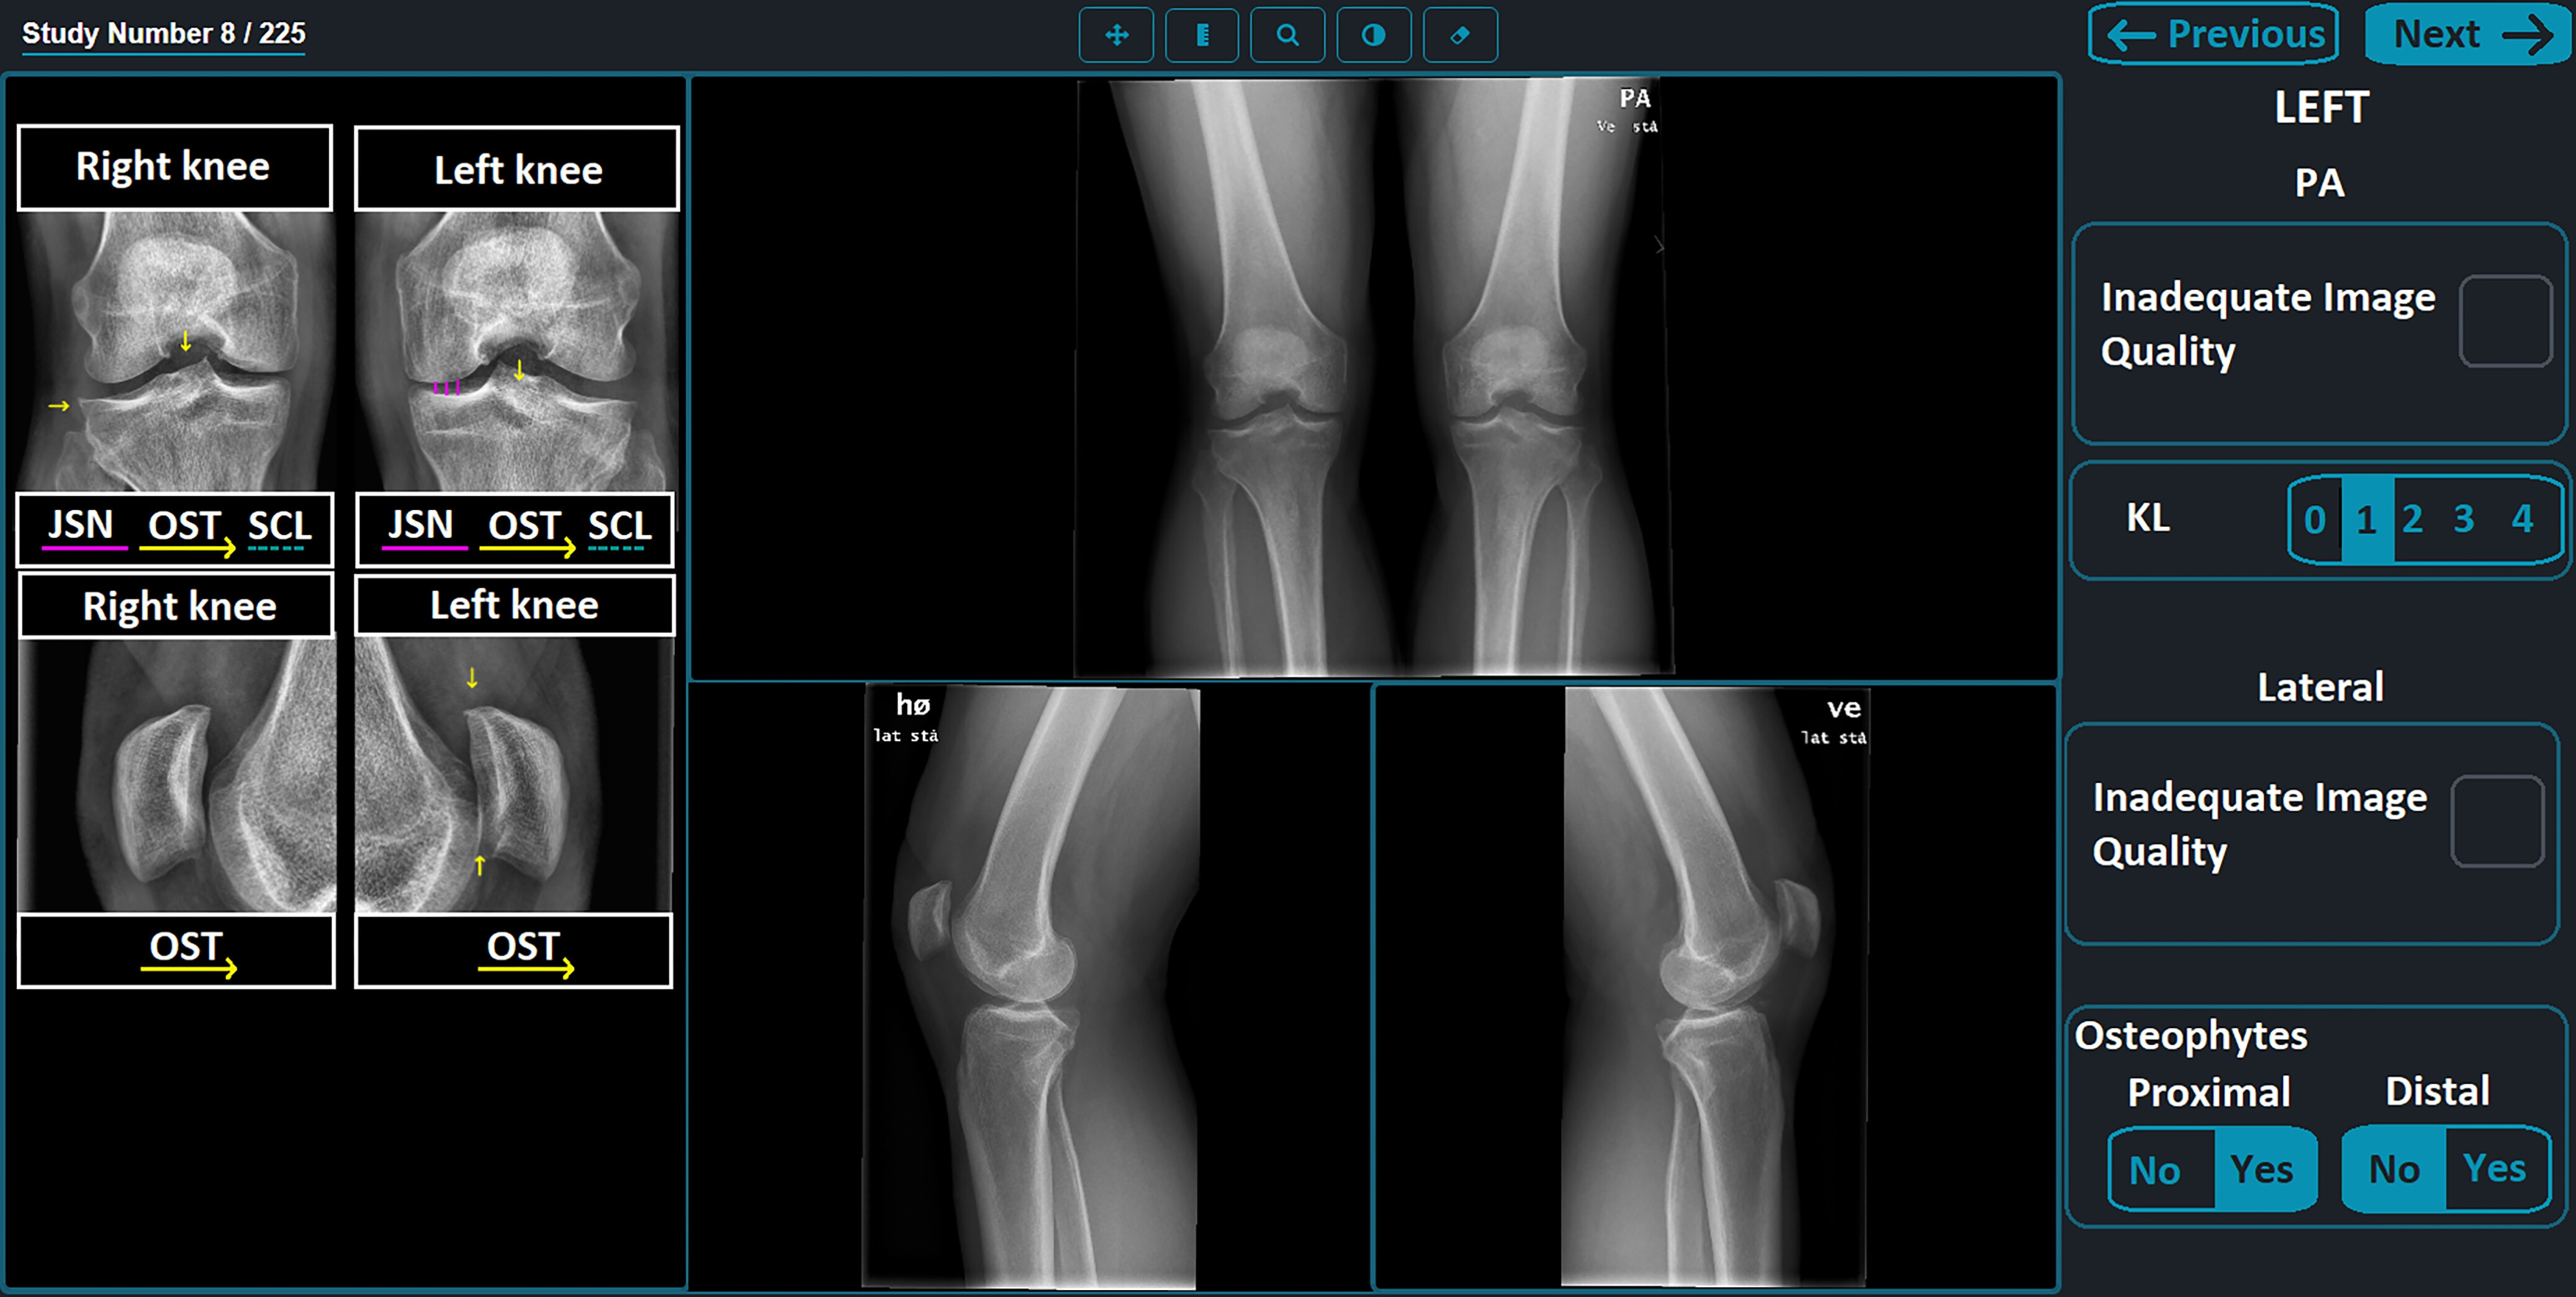

(A, B) Images with true-positive findings. Digital radiographs in (A) a 79-year-old woman with dementia and hypertension and a T-score of −3.4 and (B) an 87-year-old woman with osteoarthritis of the knee and a T-score of −2.7. The AI-enabled chest radiography mainly focused on the vertebrae and ribs around patient’s heart and lung field.Images and caption courtesy of the RSNA.